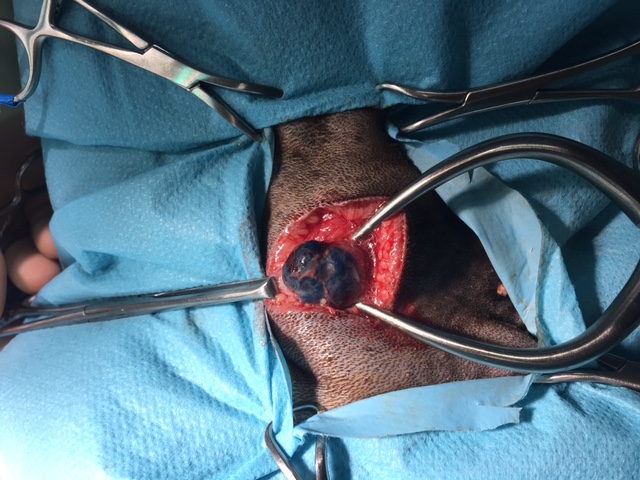

Peritumoral injection of contrast agent was then used as a type of indirect lymphography. In Cadbury’s case, the lymphatics could be traced from the tumour site to one of the submandibular lymph nodes which were therefore identified as the SLN (Figure 3). Peritumoral vital dye was then injected and Cadbury was taken to theatre where the dye had drained along the lymphatics to colour the SLN blue aiding its identification (fig 4).

Figure 4: SLN stained blue allowing easy identification